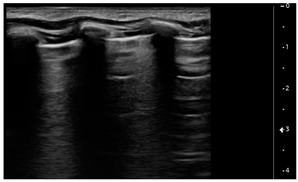

- Vertical artifacts, pleural line indented with several B-lines per field in the posterior regions

![]() | PATTERN 2 Vertical artifacts, pleural line indented with several B-lines per field in the posterior regions |